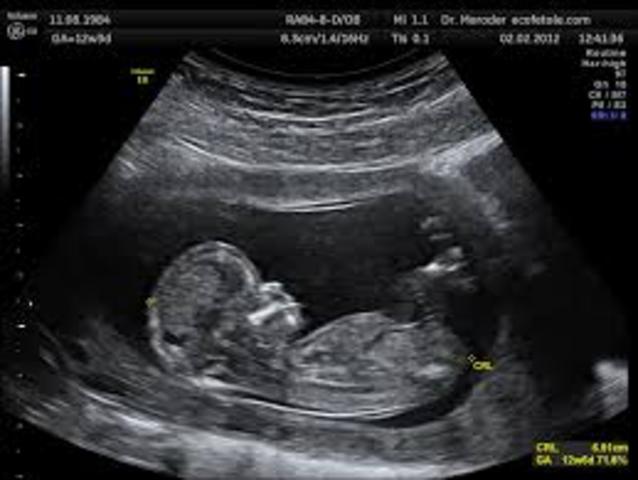

• Mi ecografía

Mi ecografía

Antes incluso de nacer, y sin ser consciente, la tecnología de una ecografía facilitaría mi vida y que yo llegase a ella